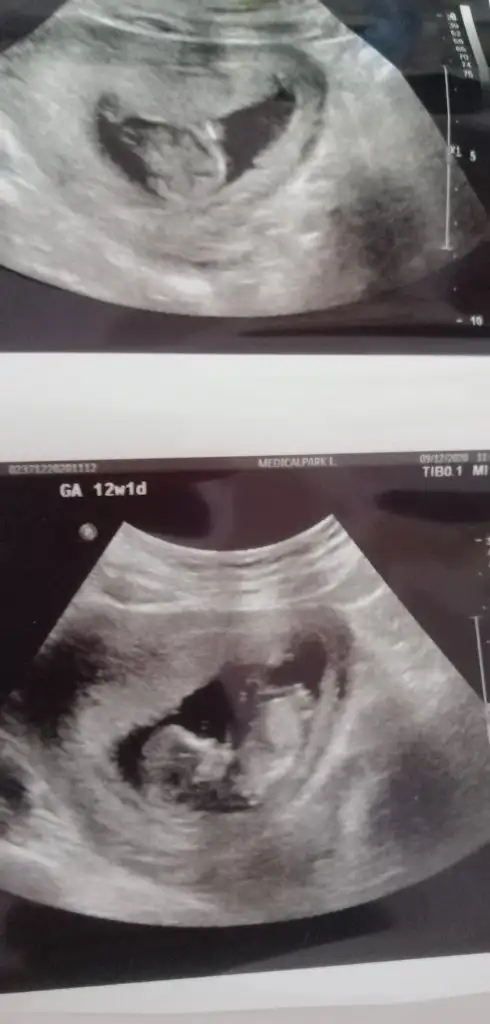

Kız gibi emin olamadım başka USG varsa paylaşın 11 12 13 haftalar olmalı

İkra meyra bana da bakarmısınız lütfen çook merak ediyorum bebeğimin cinsiyetini

Malesef başka görüntüm yok ilk kız siz dediniz inşallah öyledir 🤲🤲🤲🤲 bir hafta sonra randevum var ozaman yazarım foto yollarım

Bir hafta nasıl dayanacaksin, ben dayanamazdım, yani dayanırım da düşün düşün bir hal olurdum. :) prenses geliyordur insallah :)